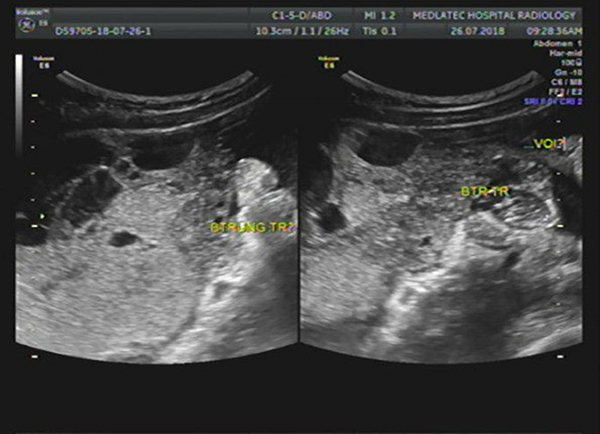

Hiện nay, siêu âm là cách thức nhanh và tốt nhất để phát hiện U nang buồng trứng. Do đó, nếu bạn muốn kiểm tra buồng trứng của mình, đừng băn khoăn liệu: siêu âm có phát hiện được U nang buồng trứng hay không. Vì chắc chắn 100% là có.

Với máy móc tiên tiến và hiện đại. Các đời máy siêu âm hiện nay có thể phát hiện được U nang trong giai đoạn sớm. Từ đó, giúp bệnh nhân có được các phương án theo dõi khám bệnh và điều trị kịp thời. U nang buồng trứng có thể chữa khỏi, tuy nhiên nếu để kéo dài không phát hiện, có thể gây ra biến chứng nguy hiểm.

Siêu âm có phát hiện U nang buồng trứng, nhưng để nắm rõ nhất tình trạng bệnh của mình, bạn nên chọn cơ sở khám bệnh uy tín. Một bác sĩ giàu kinh nghiệm mới có thể đọc kết quả siêu âm chính xác nhất và đưa ra phương án điều trị U nang buồng trứng tốt nhất.

- Siêu âm: cách thức để phát hiện xem bệnh nhân có bị U nang buồng trứng không